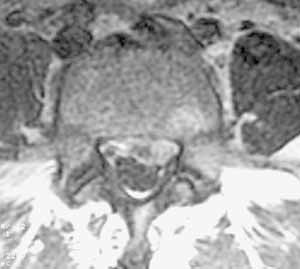

Рис 1. Большая секвестрированная грыжа диска L5-S1. (Слева) Сагитальный скан до контрастирования. (Справа) Аксиальный скан после введения магневиста.